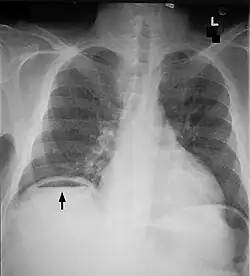

| Frontal chest X-ray. The air bubble below the right hemidiaphragm (on the left of the image) is a pneumoperitoneum. | |

Pneumoperitoneum is pneumatosis (abnormal presence of air or other gas) in the peritoneal cavity, a potential space within the abdominal cavity. The most common cause is a perforated abdominal organ, generally from a perforated peptic ulcer, although any part of the bowel may perforate from a benign ulcer, tumor or abdominal trauma. A perforated appendix rarely causes a pneumoperitoneum.

When present, pneumoperitoneum can be seen on projectional radiography, but small amounts are often missed, and CT scan is nowadays regarded as a criterion standard in the assessment of a pneumoperitoneum.[18] CT can visualize quantities as small as 5 cm3 of air or gas.

Signs that can be seen on projectional radiography are shown below: